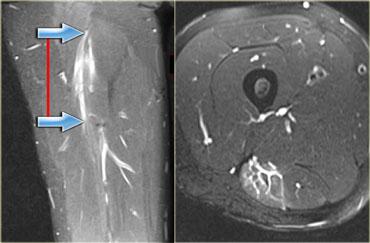

Khi phân độ chấn thương cấp tính, cần xem xét không chỉ cấu trúc mô học mà còn cả chiều dài của cơ.

Các nghiên cứu đã chỉ ra rằng chiều dài của vùng căng cơ là yếu tố tiên lượng tốt nhất cho thời gian mất khả năng vận động, với các tổn thương dài hơn đòi hỏi thời gian hồi phục lâu hơn.

(Tài liệu tham khảo của Tiến sĩ Connell DA và cộng sự, AJR 2004, 83: 975-984).

Do đó, tổn thương càng dài thì thời gian lành thương càng kéo dài.

Bên trái là hình ảnh bệnh nhân bị tổn thương cơ bụng chân độ 2.

Có tổn thương độ thấp ở đầu ngoài.